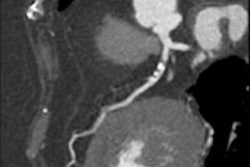

CCTA finds significant coronary artery disease in symptomatic 64-year-old man. Patient has hyperlipidemia and a family history of coronary disease; is an ex-smoker. Patient also underwent a nonspecific pathologic stress test. All images courtesy of Dr. Fabian Plank.

Two years (680 days) later, patient had ACS (STEMI), right coronary artery (RCA) stenosis of 100%, CKmax 1,416 ng/dL, TNTmax 3,315 ng/L.CCTA is a highly accurate modality for these patients, he stated. SPECT and MRI are performed less often owing to limited availability and high cost, especially locally in a largely rural atmosphere where few scanners are available.